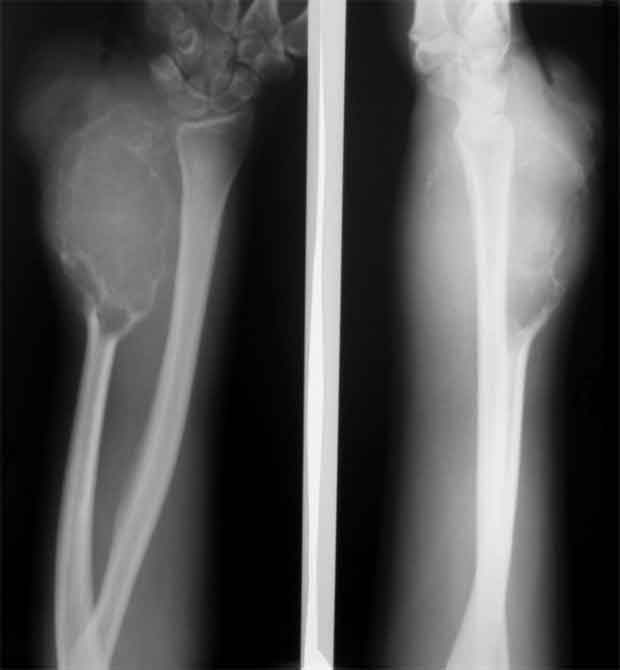

Привет, Максим! рентгенологически явные признаки малигнизации ГКО.

Летом 07 года пациентка 17 лет была прооперирована в детском отделении (рентгенологическая картина та же, гистология(от онкологов, открытая биопсия) - остеобластокластома литический вариант без признаков малигнизации.

Уважаемые коллеги, госпитализировали, наконец, эту пациентку, чему не очень рады, как клиническая, так и рентгенологическая картины изменились, кроме того Hb 76.Направил на повторную консультацию к онкологу. Остеобластеокластома может себя так вести?

Клинико-рентгенологически очень похоже на хондросаркому..... Хотя, конечно же, необходимо гистологическое заключение...

Плоховато она выглядит на снимках.

Уважаемые коллеги. По данным рентгенограммы опухоль больше похожа на злокачественную фиброзную гистиоцитому или телеангиоэктотический вариант остеогенной саркомы с поражением кожных покровов. По данным 6 отделения ЦИТО (Бурдыгин В.Н., А.В. Балберкин) и докторской диссертации А.Н. Махсона при поражении низкодифференцированной, т.е. высокозлокачественной опухолью кожных покровов или магистральных сосудисто-нервных структур органосохраняющие оперативные методы лечения не показаны, т.к. имеются отдаленные не диагностируемые метастазы. Показано комбинированное оперативное лечение по принципам неоадъювантной ПХТ.

Может при озлокачествлении (литическая форма), но уж больно похоже на хондро SA.